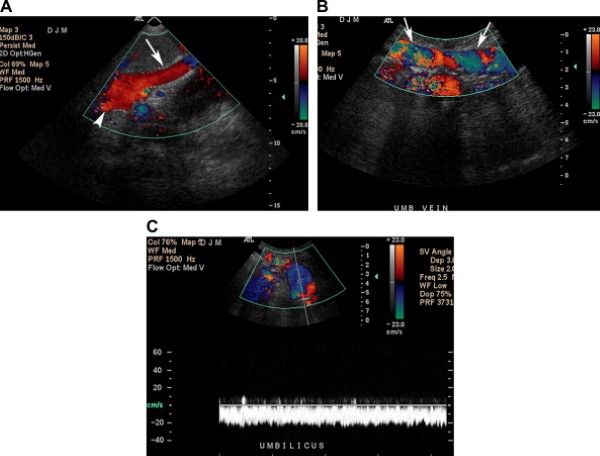

Tĩnh mạch cạnh rốn thông (Patent paraumbilical vein)

Tĩnh mạch cạnh rốn (tái thông) là một mạch máu bàng hệ cửa-chủ phổ biến, dễ phát hiện bằng siêu âm trong bệnh cảnh tăng áp lực tĩnh mạch cửa, đặc biệt trong các trường hợp xơ gan do rượu [5]. Tĩnh mạch này đi theo dây chằng tròn trong dây chằng liềm khi nó mang máu từ ngành trái tĩnh mạch cửa tới các tĩnh mạch thượng vị sâu và nông ở thành bụng [1]. Người ta cho rằng tĩnh mạch cạnh rốn thông có thể bảo vệ bệnh nhân khỏi xuất huyết nặng do giãn vỡ các tĩnh mạch thực quản.

Trên siêu âm, tĩnh mạch cạnh rốn có dạng cấu trúc hình ống, trống âm, đường kính ít nhất 3mm, chạy ra trước và xuống dưới từ ngành trái tĩnh mạch cửa hướng tới thành bụng trước. Siêu âm Doppler màu chứng minh phổ dòng chảy tĩnh mạch kiểu một pha [1]. Các tĩnh mạch thành bụng trước giãn ngoằn ngoèo, “hình đầu sứa”, cũng có thể nhìn thấy rõ ở mô dưới da vùng quanh rốn, nhất là khi dùng đầu dò thẳng (Hình 13).

Hình 13. Tĩnh mạch cạnh rốn thông ở bệnh nhân nữ 51 tuổi có tiền sử xơ gan do nghiện rượu. (Hình A) Ảnh siêu âm màu cắt đứng dọc qua thùy trái gan cho thấy một tĩnh mạch to, chạy từ ngành trái tĩnh mạch cửa (đầu mũi tên) đến thành bụng trước (mũi tên). (Hình B) Ảnh siêu âm Doppler màu cắt dọc tĩnh mạch ngoằn ngoèo ở thành bụng trước chạy tới rốn. (Hình C) Ảnh siêu âm Doppler trình bày sóng tĩnh mạch trong mạch máu thăm dò, khẳng định chẩn đoán tĩnh mạch cạnh rốn tái thông.